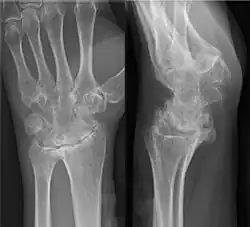

Ankylosen der Handwurzelknochen nach einer abgelaufenen juvenilen Arthritis.

Die Ankylose (griechisch ἀγκύλωσις ánkylosis „Verkrümmung“, bei Galenos „Verwachsung“ in Bezug auf narbig verwachsene Augenlider, ab dem 7. Jahrhundert bei Paulos von Aigina auch „Gelenkversteifung“,[1] von ἀγκύλος „gebeugt, gebogen“), älter auch griechisch-lateinisch und englisch[2] Anchylosis,[3] ist der medizinische Fachausdruck für eine vollständige Gelenksteife. Diese kann bedingt sein durch Verknöcherung des Gelenkspalts oder durch Veränderungen (Narbenzüge) der Gelenkkapsel.[4] Häufig handelt es sich um bestimmte (ankylosierende) Wirbelleiden[5] oder die Folge einer entzündlichen Destruktion, z. B. bei rheumatoider Arthritis.[6] Davon zu unterscheiden ist die Zahn-Ankylose, die (dentoalveoläre) Ankylose der Zähne.[7] Ankylosierung beschreibt den Vorgang der Gelenkversteifung.[8]